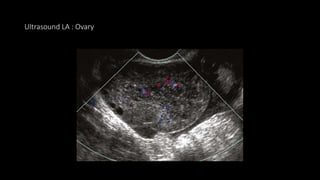

 USG

• Torsion is characterized by an heterogeneous enlarged ovary with internal echoes

Ultrasound LA : Ovary